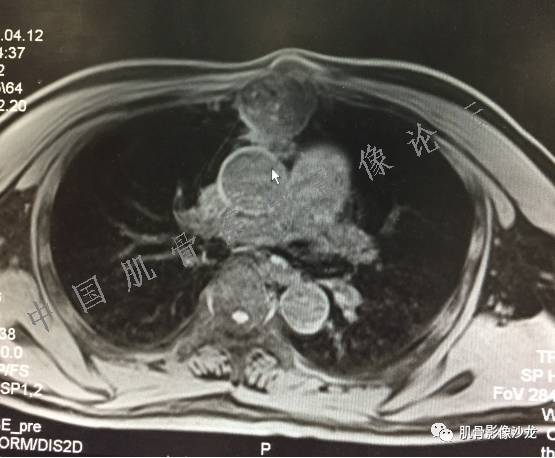

患者2月前无明显诱因下感右腿疼痛、麻木,疼痛呈持续性,发作时无法行走,休息后可缓解。当时无明显肿块,患者遂至当地医院就诊,查X片见右髂骨骨质破坏。6周前患者自觉右髋部渐大肿块,初肿块较小,后肿块逐渐增大,现肿块约12*10cm大小,有压痛。患者遂至我院就诊,查MRI:右髂骨异常信号,伴软组织肿块。ECT、肺CT未见转移。现患者为求进一步治疗,门诊拟“右髂骨肿块 ”收治入院。 患者发病来,神清,精神可,胃纳夜眠可,二便无殊,体重无明显变化。

信号 飞鹰行动:的确应该考虑软骨类肿瘤

飞鹰行动 : 软骨肉瘤内也有纤维组织的

飞鹰行动 : 第一列可以看见T2小结节样高信号,周围有纤维组织环绕

高回青 : 另外还可以见到扇贝状分叶